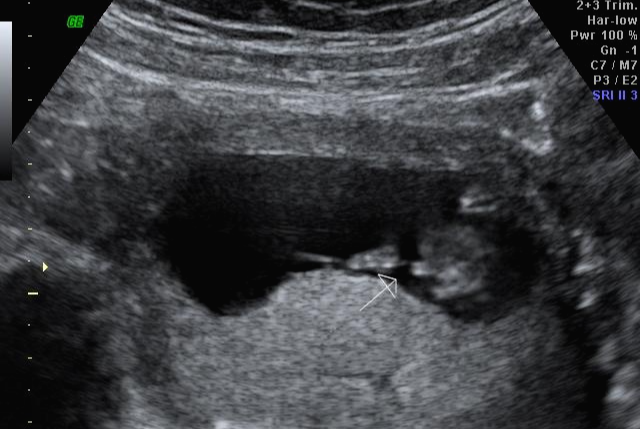

그리고 초음파 봐주시는 분께서 13주차가 되면 정확히 알 수 있으니 다음 주에 오라고 하셔서 일주일 뒤 다시 방문을 했습니다. (위에 사진은 12주 차 때 아들이라고 보여주신 초음파 사진이에요~ 화살표 보면 툭 튀어나와있는 부분을 보여주면서 아들이라고 하셨어요~)

아 진짜 전문가는 다르구나~ 이렇게 이른 주수에도 성별을 알 수가 있구나 생각을 했지만 이 시기 때는 성별을 정확히 알 수 없다는 글들을 봐서 살짝~ 의심스럽기도 했지만 그래도 100프로라니깐 ㅎㅎ 믿어보았어요~ 근데 위에 사진을 보면 성별을 알 수 있는 각도 법이 있는데 각도가 딸 같아서 긴가민가~하긴 했지만 의심은 잠시! 전문가 분을 믿기로 ㅋㅋㅋㅋ